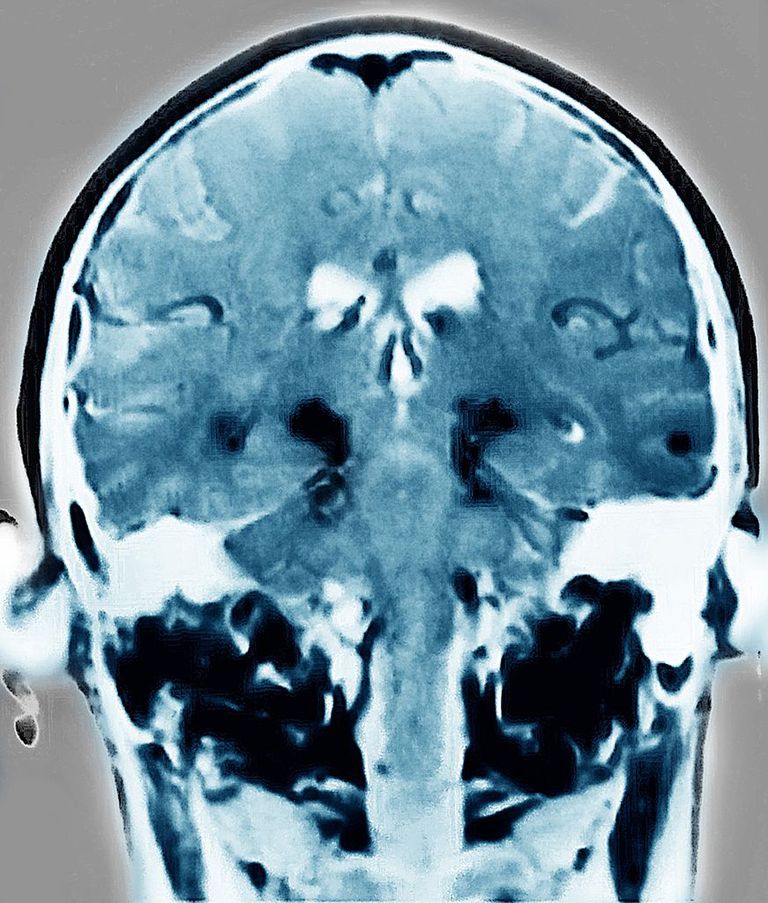

Una nueva tecnología permite “ver” el dolor

Ayudará a pacientes inconscientes o con problemas emocionales...